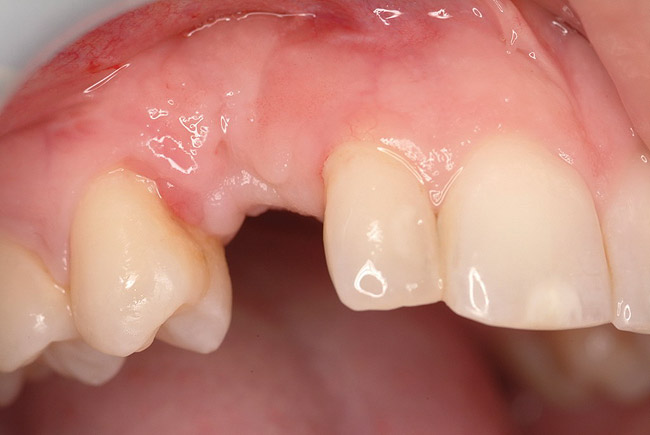

Figure 1  In Case 1, the patient’s edentulous site appeared healthy, with significant keratinized mucosa in the canine position.

Figure 1

A 26-year-old woman presented with a history of trauma combined with an impacted maxillary right canine (No. 6), which was extracted in early childhood. Following two courses of orthodontic therapy—one in her early teens and the second in early adulthood—the area had reportedly been grafted approximately 9 months prior to her initial presentation to the author’s private periodontal practice. Clinically, the edentulous site appeared healthy, with significant keratinized mucosa in the canine position (Figure 1). A cone-beam CT scan revealed severe horizontal bone deficiency in the proposed implant position (Figure 2). Adequate bone height for implant placement was evident; however, the thinnest portion of the ridge measured approximately 0.45 mm in width. It was proposed that an augmentation be performed to facilitate implant placement, which the patient accepted.